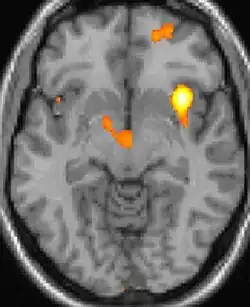

Positron emission tomography (PET) shows brain areas being activated during pain.

Positron emission tomography (PET) scans indicate the brain areas which are activated during attack only, compared to pain free periods. These pictures show brain areas that are active during pain in yellow/orange color (called "pain matrix"). The area in the center (in all three views) is activated only during cluster headaches. The bottom row voxel-based morphometry shows structural brain differences between individuals with and without CH; only a portion of the hypothalamus is different.[36]